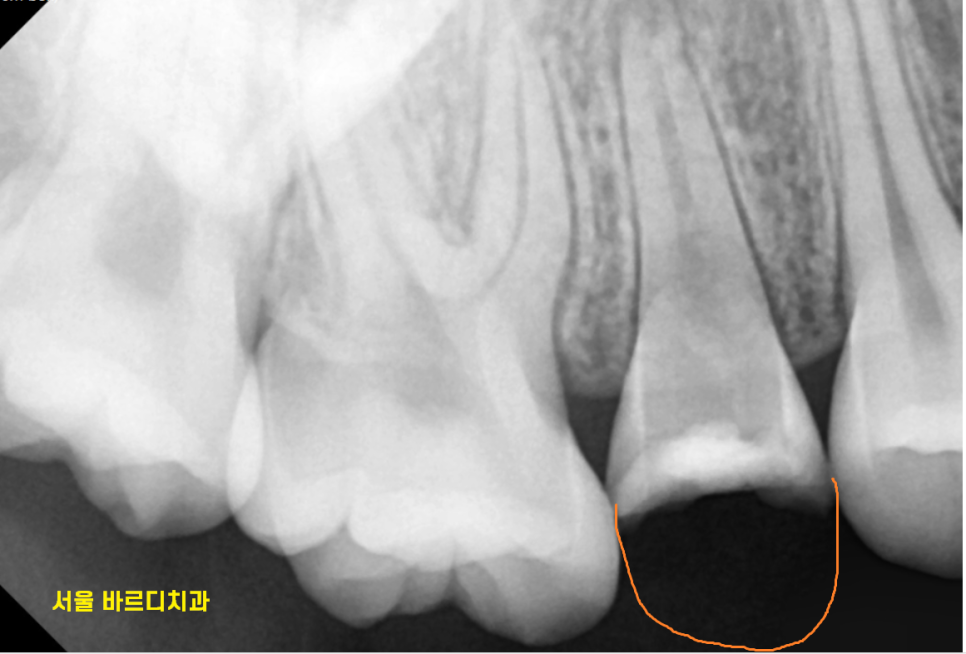

환자분은 x-ray를 찍어보았을 때

뿌리 끝에 염증이 없고

치아 흔들림이 없기에

살려볼 수 있었는데요.

치아가 뿌리쪽까지 부러지긴 했지만

절반 정도가 남아 있어서